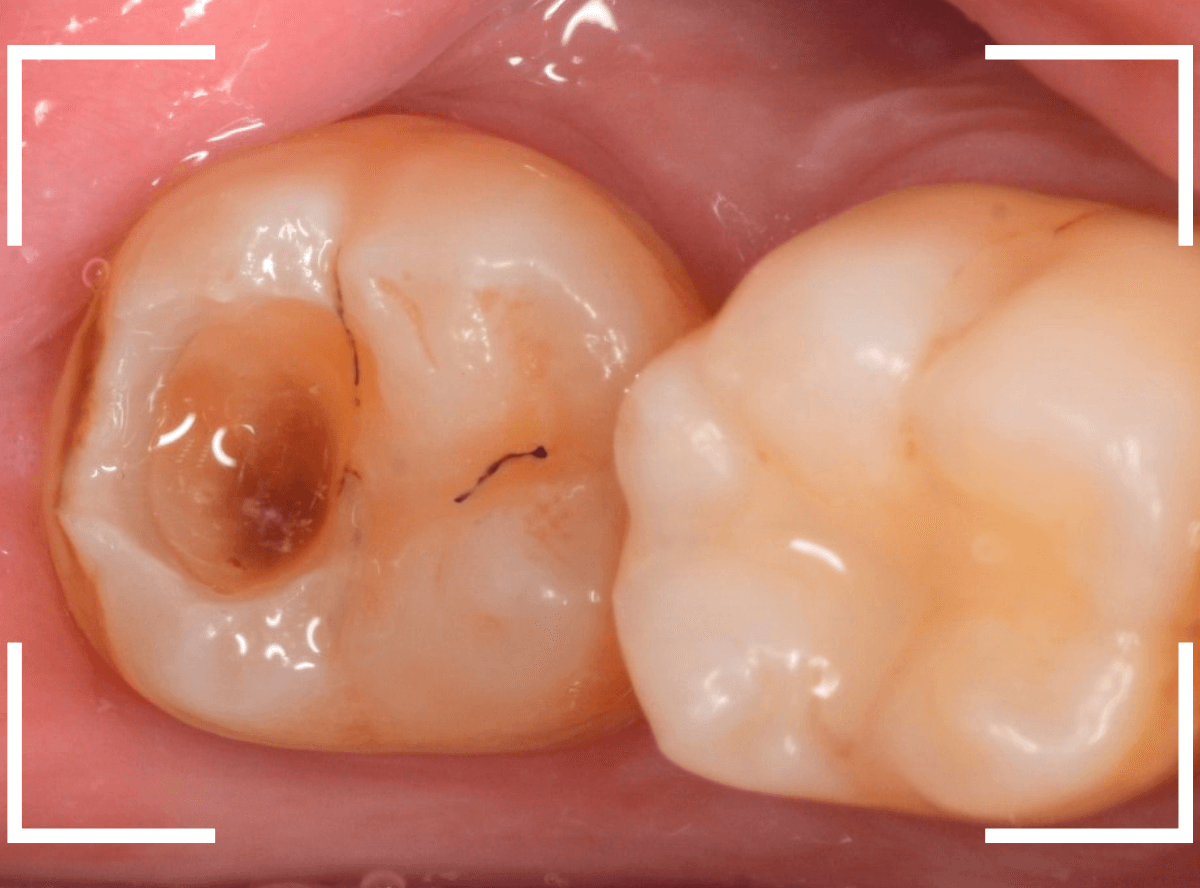

奥歯で咬んだ時に、痛みを感じるという訴えで来院された患者さんです。

パッと見は特に問題なさそうな状態ですが、大きなレジン治療がしてあり、レジンの奥もボヤっと黒っぽく見えてアヤシイ感じです。

レントゲン写真で確認します。

青い線が神経、赤い線が虫歯です。

神経に触ってしまいそうなほどの大きな虫歯です。

(隣の歯も虫歯がありそうです)